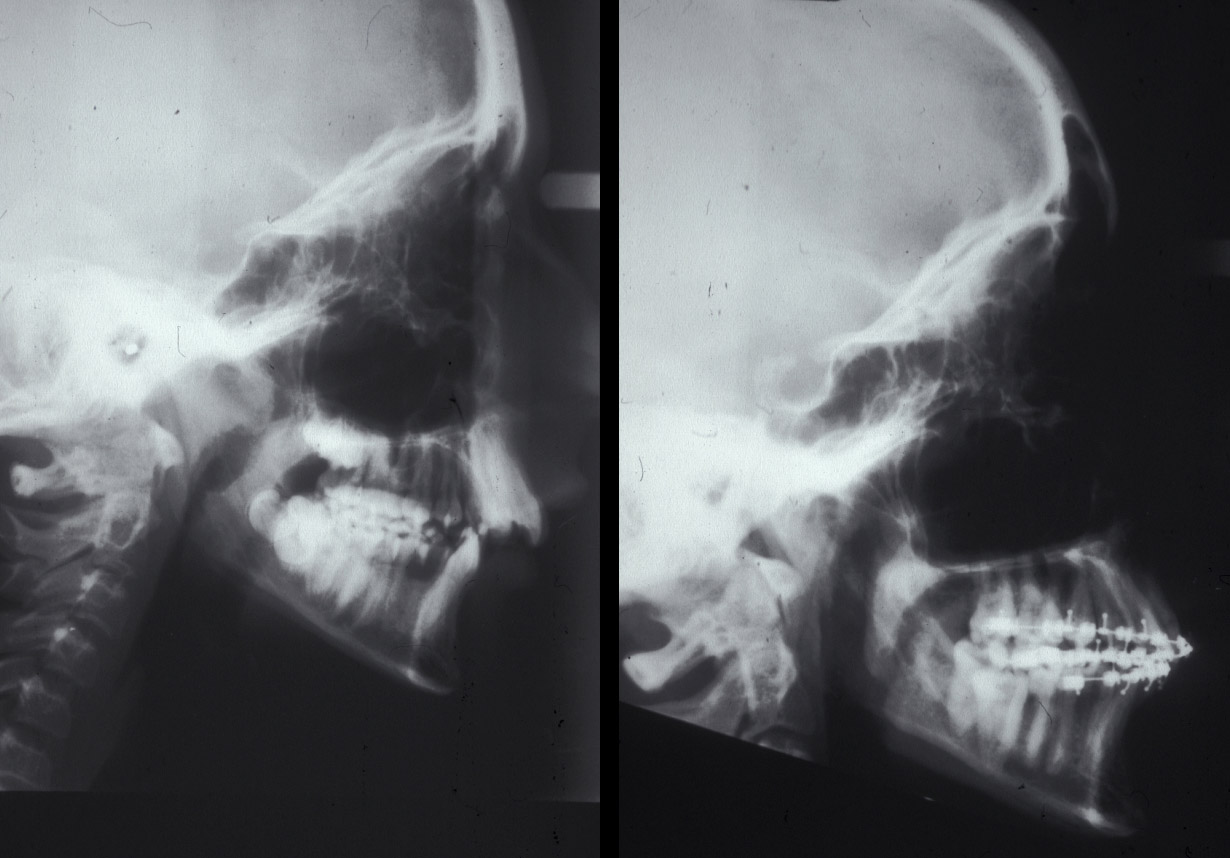

Figure 17: Lateral cephalograms of a case of class II malocclusion before (left) and during (right) orthodontic decompensation.